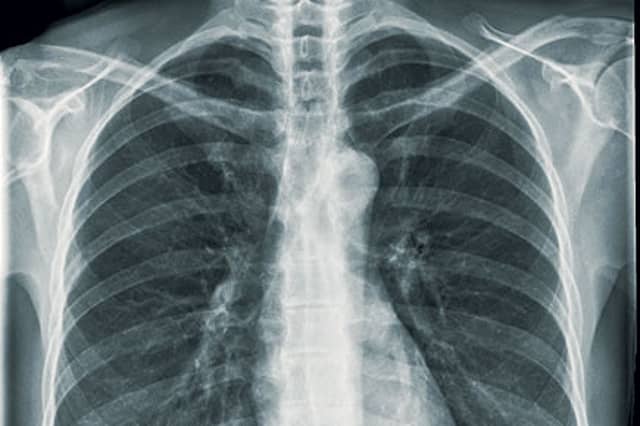

Tuberculosis remains one of the world's leading health threats, despite a century of effort directed at combating the disease. Estimates suggest that a third of the world's population is infected by TB, and even today over two million people die of the disease every year. One of the reasons the bacteria causing TB—Mycobacterium tuberculosis (Mtb)—is such a threat is that it seems to be able to render the body's immune defences useless. Now a recent paper published in Proceedings of the National Academy of Sciences provides an answer to how Mtb is able to manage this feat.